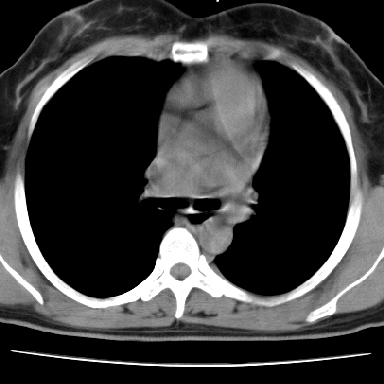

f 37 咳嗽1周,咯血1次,无浓痰,无明显发热

左下肺肿块影,内可以见小泡征,并见厚壁空洞形成,洞内缘凹凸不平,可见壁结节。靠近胸膜侧可见胸膜凹陷征。左侧胸腔内可见少量低密度积液影。右肺可见两处高致密的小结节影。

考虑:左下肺周围型肺癌伴右肺转移

左下肺肿块影,内可以见小泡征,并见厚壁空洞形成,洞内缘凹凸不平,可见壁结节。靠近胸膜侧可见胸膜凹陷征。左侧胸腔内可见少量低密度积液影。双肺可见多发性小结节影。

考虑:左下肺癌性空洞伴两肺转移

左下肺有空洞,壁厚薄不均,壁结节,两肺多发小结节影,腋窝下可疑淋巴结肿大,综上所述考虑周围性肺癌并两肺转移可能性大,建议穿刺活检。

右肺多发小结节影,边界清楚,符合转移瘤的特点;2、左下肺偏心性空洞影,右侧乳腺内高密度影,需要查体除外右侧乳腺肿瘤;3、腋窝淋巴结肿大,考虑转移。